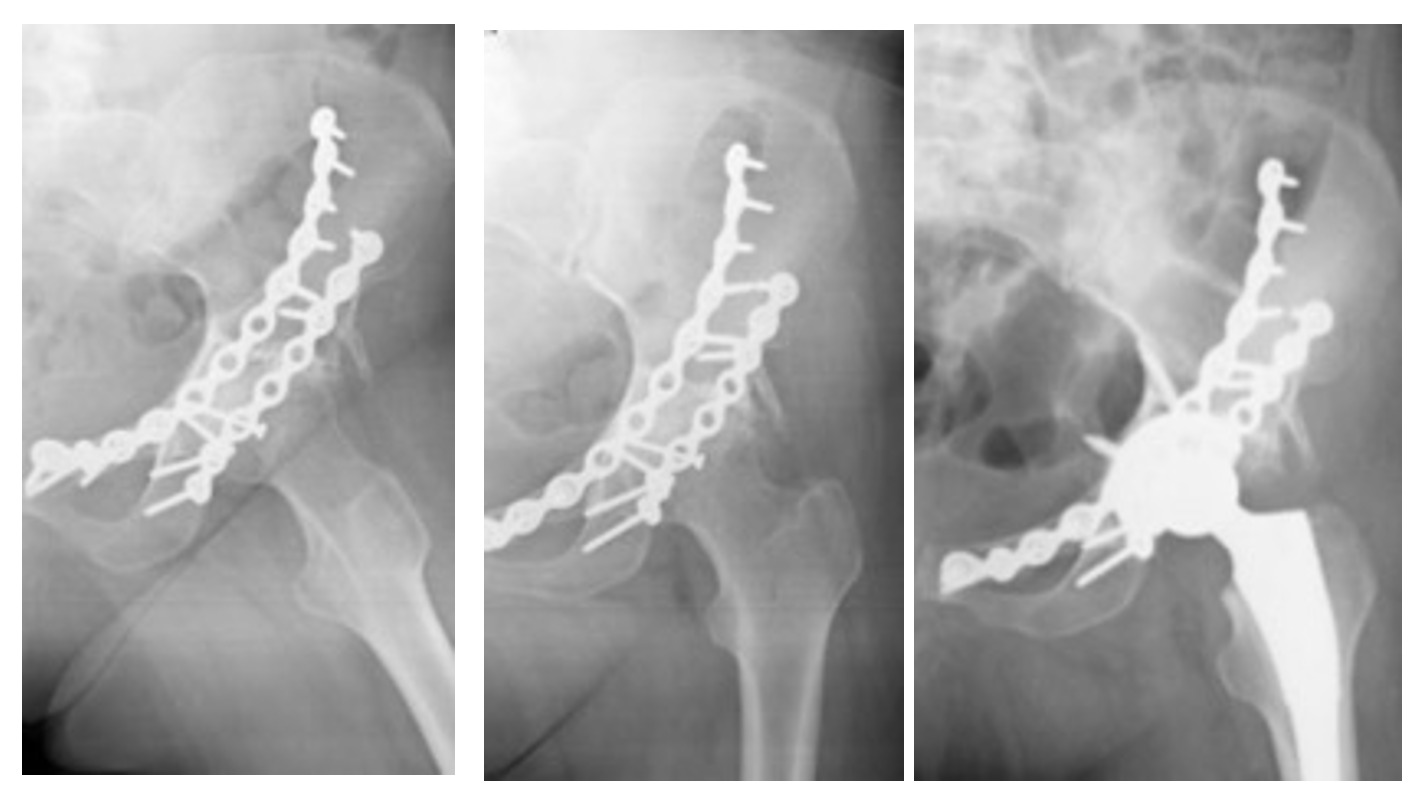

Of the 31 patients who had previously undergone ORIF, 3 underwent reduction and osteosynthesis with screws for marginal fractures, 14 underwent posterior stabilization, 8 underwent anterior stabilization and 6 underwent antero-posterior stabilization (Fig.2a-b-c).